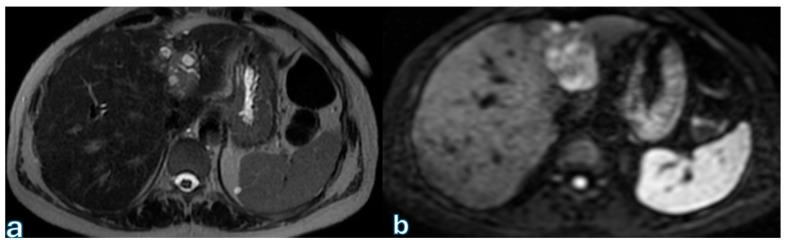

Radiological assessment following pancreaticoduodenectomy is critical for the prompt diagnosis and management of postoperative complications, significantly influencing patient outcomes. Pancreaticoduodenectomy, or the Whipple procedure, is the standard surgical intervention for pancreatic and periampullary malignancies, but it involves notable risks, especially from complications like fistulas, bleeding, or leakage. Cross-sectional imaging, particularly contrast-enhanced computed tomography, serves as the primary diagnostic tool due to its rapid acquisition, high resolution, and effective delineation of postoperative anatomy and complications. Magnetic resonance imaging (with cholangiopancreatography and hepatobiliary contrast agents) complements CT by providing superior contrast resolution for specific complications, notably in the biliary system and pancreatic duct. This narrative review discusses various imaging techniques and their applications, highlighting characteristic radiological features of common postoperative complications. It underscores the importance of a multidisciplinary approach, emphasizing close collaboration between radiologists and surgeons to optimize surgical decision-making and improve patient management post-pancreatic surgery.

胰十二指肠切除术后的影像学评估对于术后并发症的及时诊断和处理至关重要,对患者预后有显著影响。胰十二指肠切除术,即惠普尔手术,是治疗胰腺和壶腹周围恶性肿瘤的标准外科手术,但该手术存在显著风险,尤其是瘘、出血或渗漏等并发症。横断面成像,特别是增强计算机断层扫描,因其采集速度快、分辨率高且能有效描绘术后解剖结构和并发症,成为主要的诊断工具。磁共振成像(结合磁共振胰胆管造影和肝胆对比剂)通过为特定并发症提供更高的对比分辨率来补充CT,尤其是在胆道系统和胰管方面。本叙述性综述讨论了各种成像技术及其应用,突出了常见术后并发症的特征性影像学表现。强调了多学科方法的重要性,强调放射科医生和外科医生之间密切合作,以优化手术决策并改善胰腺手术后的患者管理。